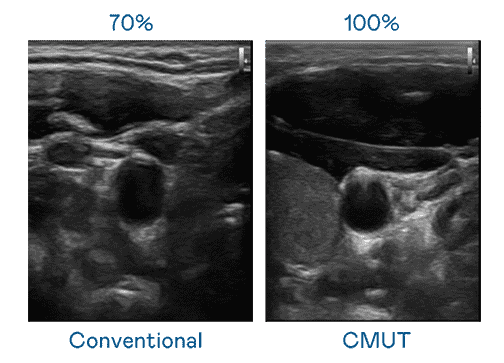

CMUT 技术是一种用电容式微机电元件来产生超音波讯号的技术。。与传统 PZT 压电式技术相比,,CMUT 频宽增加 30%,,更宽频的超音波讯号让影像解析度大幅提升,,,,是实现高影像品质医疗超音波扫描、、促进精准医疗发展的关键技术。。。。

大频宽带来超清晰影像

超音波影像的解析度高低,,首先取决于探头能发出的讯号频宽。。。。蓝狮在线 CMUT 可提供高清晰的超音波讯号,,,,提供高频宽、、高灵敏度、、、影像纹理细节更高的超音波影像,,,,协助医护人员缩短影像判读时间及利用精准的医疗影像进行诊断。。